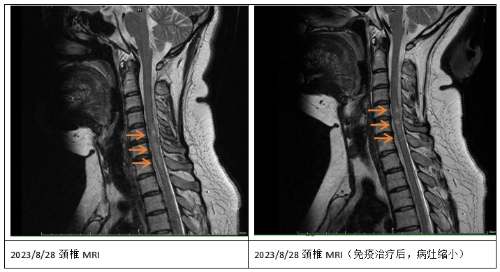

半年前,娇娇身体麻木不适的感觉加重了,再次住院时发现脊髓内又有新发较大面积脱髓鞘病灶,这次特异性抗体AQP4不仅仅在血里面存在了,脑脊液里也有1:3.2的滴度。常规的免疫球蛋白和激素治疗后,她的身体反应依然不佳。